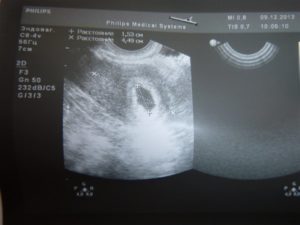

Кроме того, коричневые выделения на 7 неделе могут являться признаком патологии прикрепления плода и плацентарной недостаточности. Определить причину появления на 7 неделе беременности коричневых выделений можно при помощи УЗИ диагностики.

Обнаружить какую-либо патологию самостоятельно практически невозможно, поэтому важно отслеживать динамику развития плода с помощью ультразвуковой диагностики.

- Также кровянистая мазня может наблюдаться на седьмой неделе из-за внематочной имплантации эмбриона. Подтвердить данную патологию можно с помощью УЗИ, в ходе которого внутри маточной полости не обнаружится плодного яйца. Подобное отклонение устраняется лапароскопическим способом или с помощью специальных медикаментов.